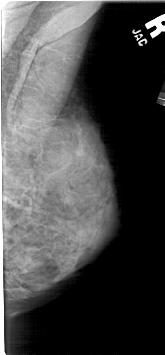

A_1684_1.RIGHT_CC

RIGHT_CC LINES 4816 PIXELS_PER_LINE 2281 BITS_PER_PIXEL 12 RESOLUTION 43.5 NON_OVERLAY